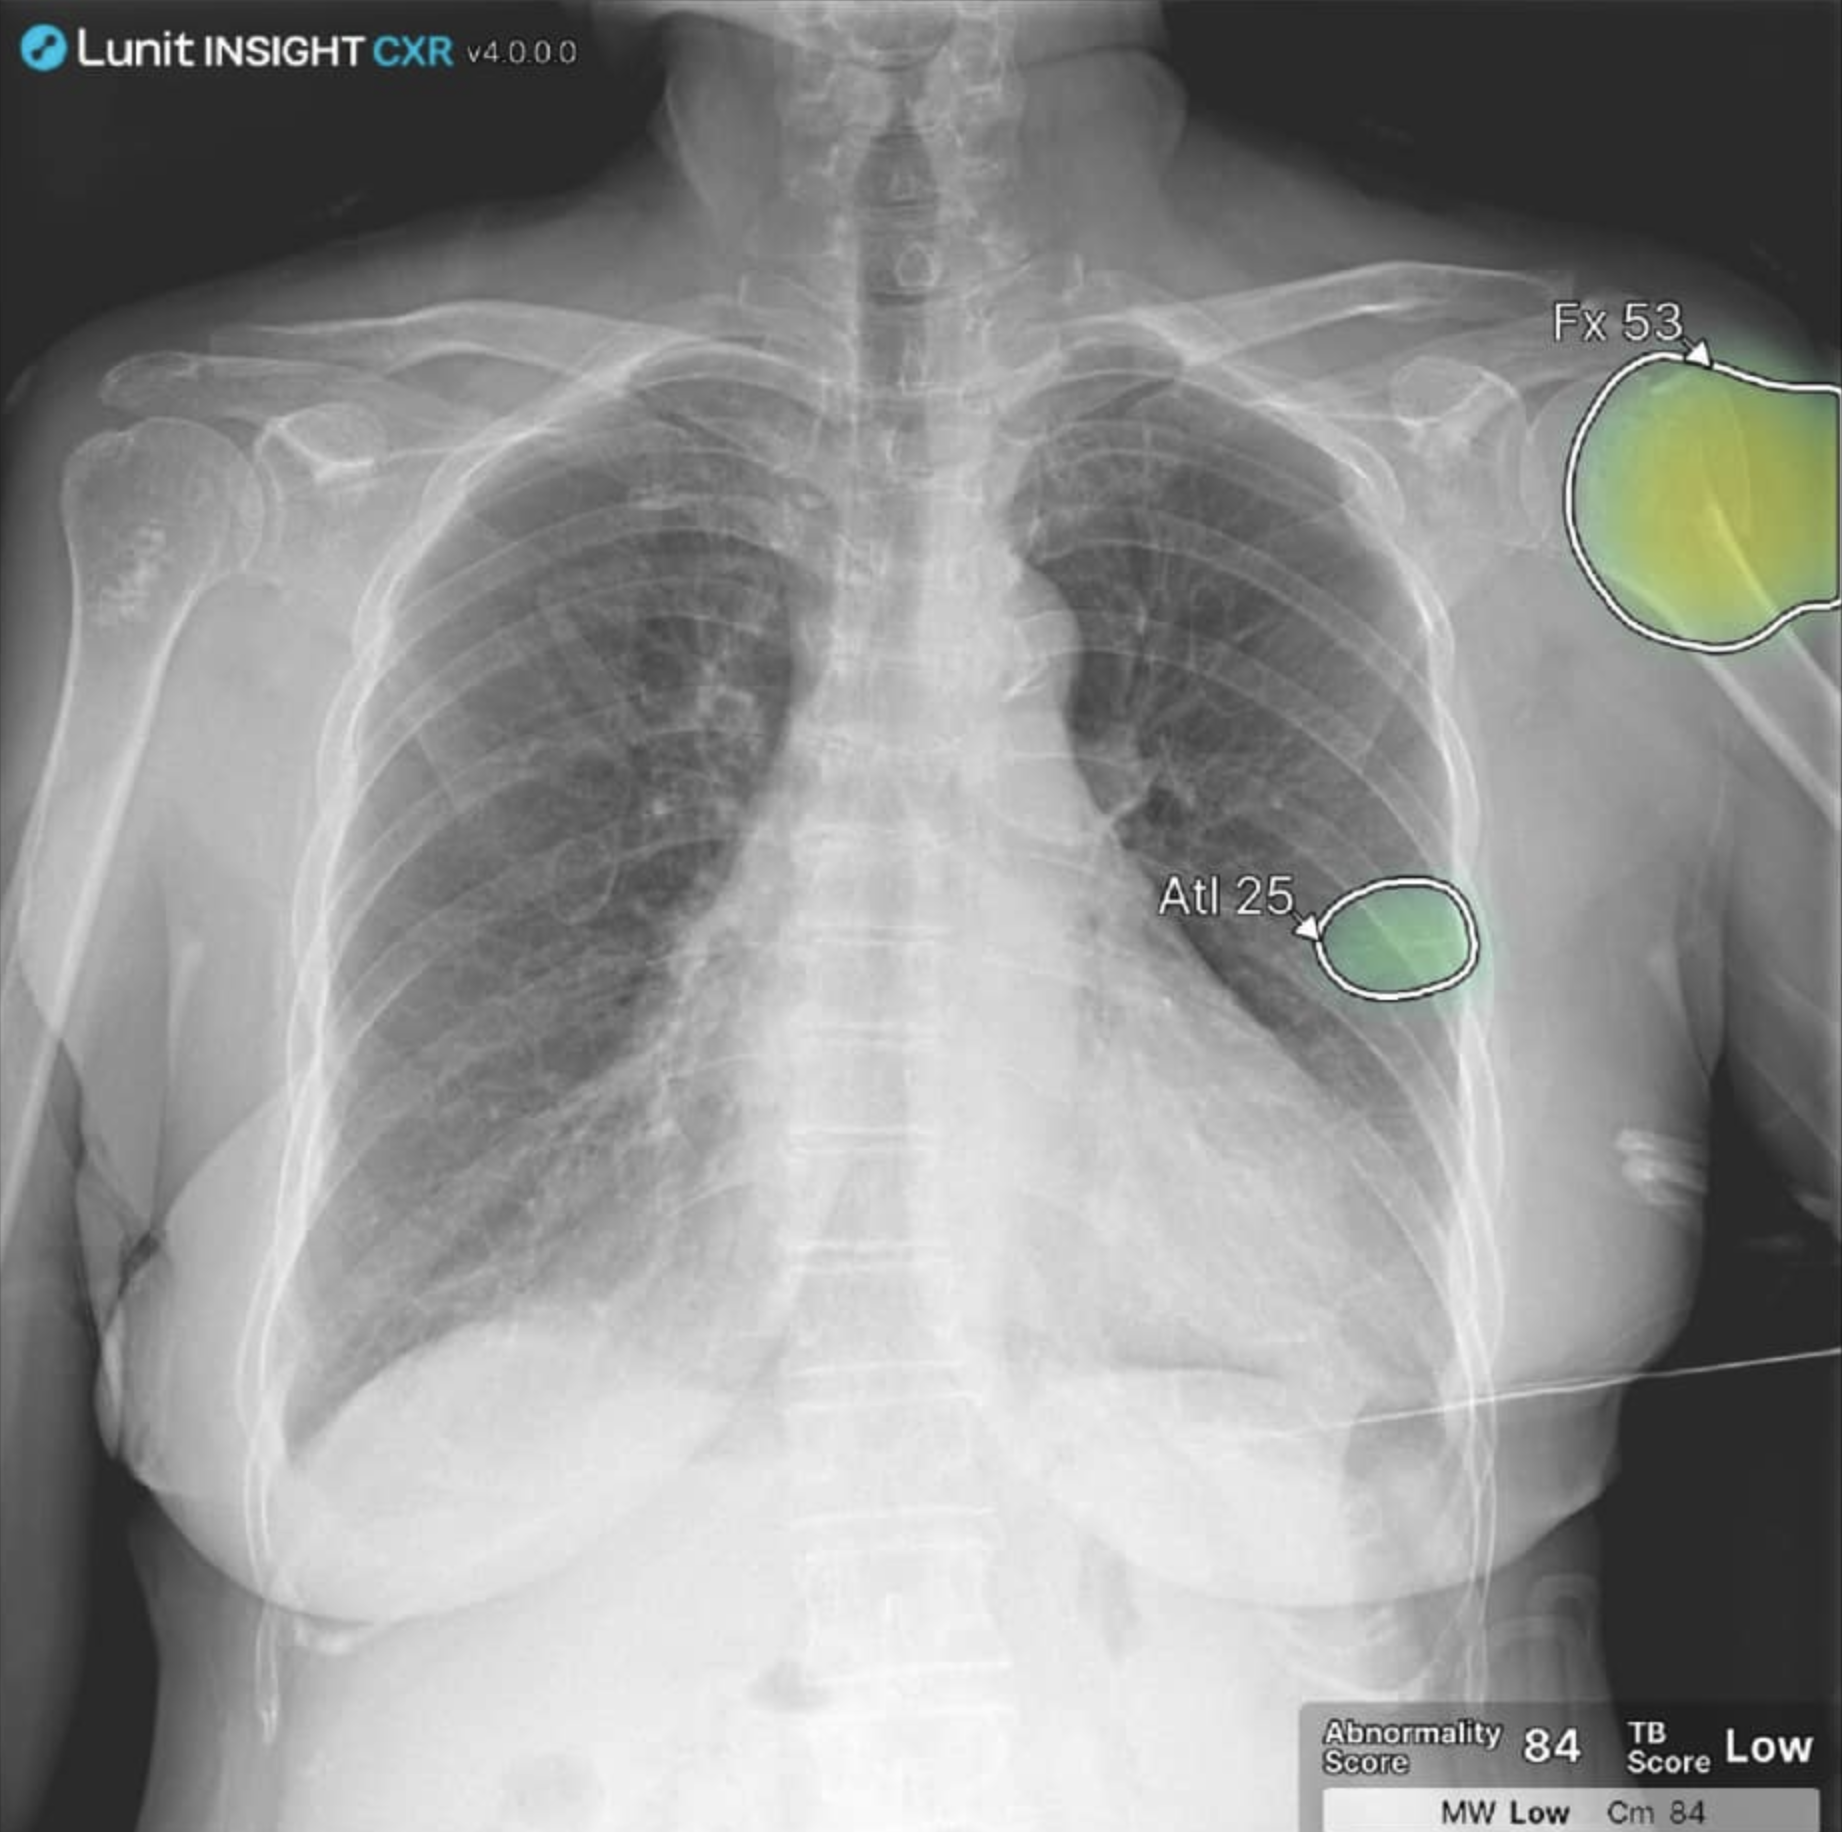

– d’ajouter des superpositions visuelles et des scores directement sur les images

– d’apporter un filet de sécurité supplémentaire pour des signes discrets (nodules, pneumothorax, épanchement pleural…)